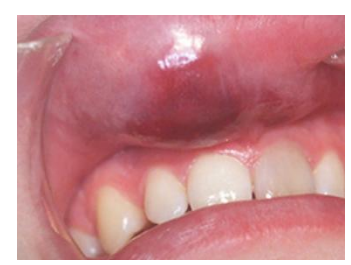

oral hematoma * swelling 1 day duration due to truma